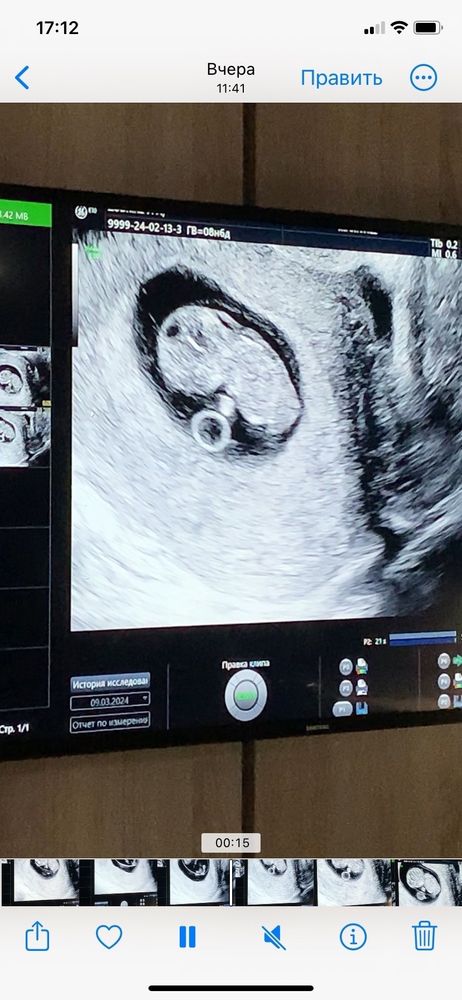

Узи 9 недель

А какое твп?

Юлия, в том то и беда, что она его не измерила, сказала, что сейчас измерять будет нечестно и некорректно вроде бы. Я ей тем же вечером написала в социальной сети, она также ответила мне, хотя я просто спросила увеличено оно или нет